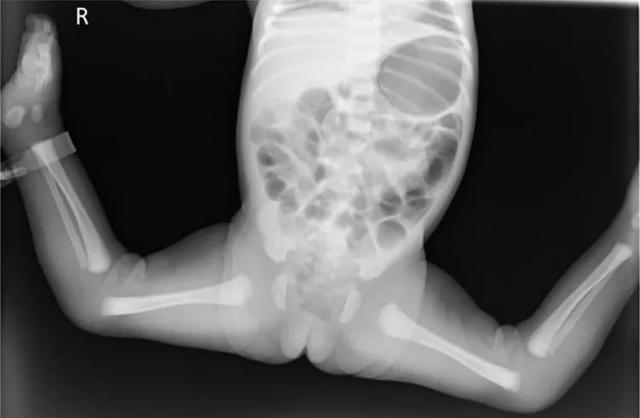

患儿,女,足月产,新生儿。生后即发现右膝关节过伸畸形请会诊。

查体:膝关节被动屈曲明显受限,膝前部皮肤皱褶明显,腘窝皮肤皱褶消失,可触及髌骨,髌骨形态大小均正常;股骨髁向后,胫骨向前移位,被动屈膝时有弹性反抗,被动活动膝关节过伸,胫骨可以前后推移,股四头肌无挛缩,髌上囊触不清,无其他畸形。

X线片示:胫骨向后移位。

临床诊断:双侧先天性膝关节脱位。